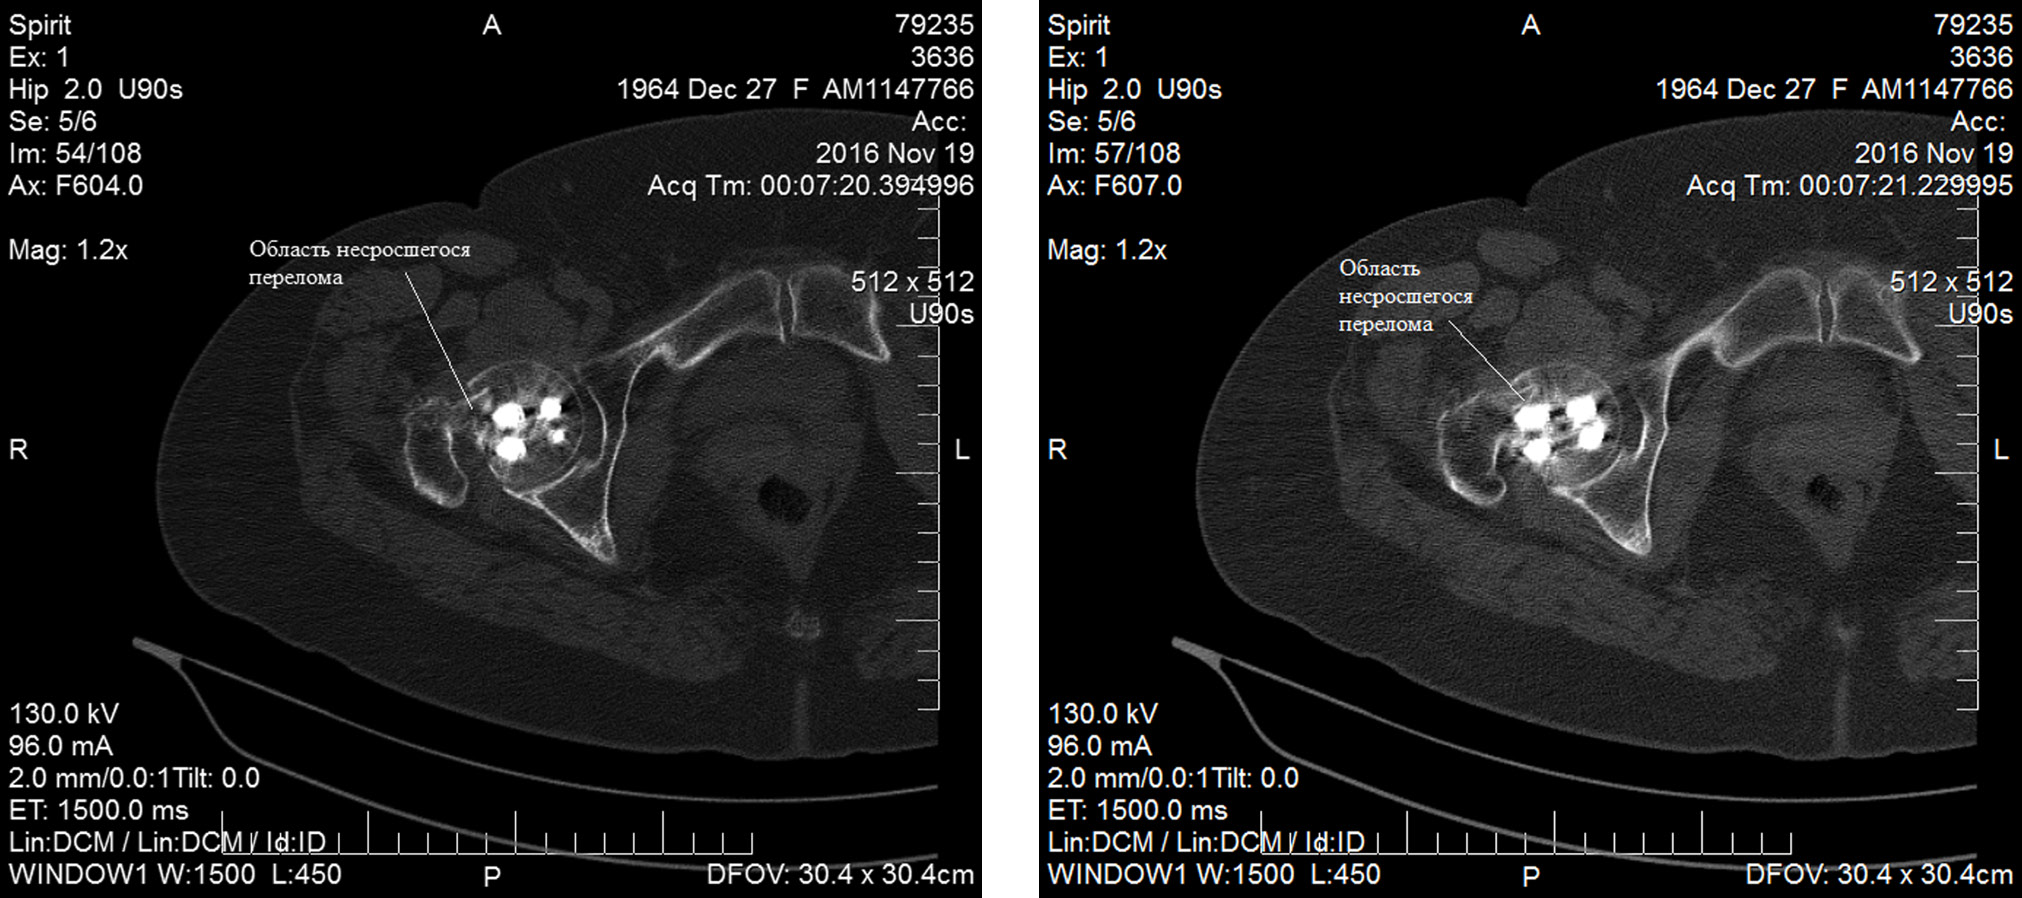

Прижизненно диагностированное несращение перелома ШБК в условиях ДДФ, сопровождающегося полным восстановлением функции нижней конечности и отсутствием болевого синдрома, иллюстрирует следующее клиническое наблюдение.

Пациентка Н., № и/б 2224-2015, 50 лет, пострадала в результате дорожно-транспортного происшествия. Через 1 час с момента получения травмы бригадой скорой медицинской помощи доставлена в клинику, диагностирован перелом ШБК справа (Garden III). На вторые сутки пребывания в стационаре выполнена операция методом ДДФ. Пациентку после выписки из стационара неоднократно приглашали на повторные исследования, однако ввиду отсутствия жалоб на приёмы она не приходила. Через 1 год с момента операции амбулаторно выполнила МСКТ таза (проведение которой не было связано с послеоперационной диагностикой), визуализированы КТ-признаки несращения перелома ШБК с формированием замыкательных пластинок в условиях ДДФ (рис. 3). При этом функция конечности и опороспособность восстановлены полностью, пациентка вернулась к привычному преморбидному активному образу жизни. Оценка качества жизни пациентки, рассчитанная с использованием опросника SF-36, соответствует хорошему функциональному результату (физический компонент здоровья — 33,5 балла, психологический — 37,2). Показатель по шкале Харриса составил 76 баллов и был оценён как хороший функциональный результат. От предложенного эндопротезирования ТБС отказалась.

Рис. 3. КТ-картина несращения перелома шейки бедренной кости у пациентки через 12 месяцев с момента операции.

Fig. 3. CT image of non-union of femoral neck fracture in a patient 12 months after surgery.

Таким образом, при наличии рентгенологически подтверждённого несращения перелома ШБК в условиях остеосинтеза с использованием методики ДДФ у этой пациентки не отмечалось ни болевого синдрома, ни функциональных нарушений нижней конечности, требующих хирургического лечения; такой клинико-рентгенологической картины мы не наблюдали ни у одного пациента с ложным суставом ШБК из группы сравнения.